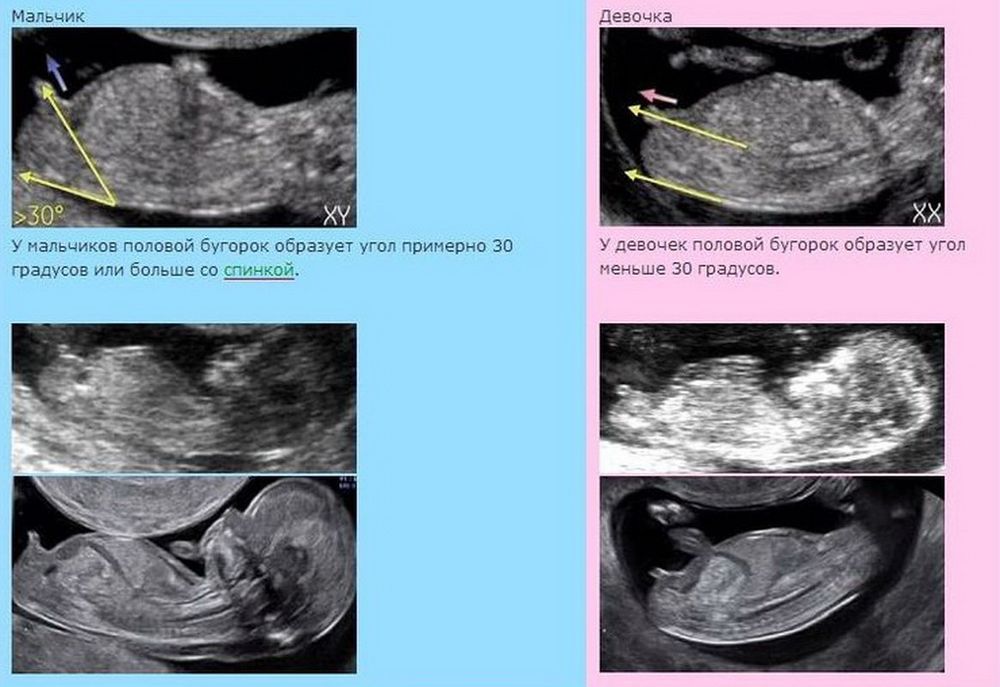

Регина в Благополучная беременность 2 года Пол ребёнка Пол малыша Девочки, какие ваши предположения?) Посмотрите еще 20 записей на эту тему Лучший ответ Mommy По бугорку на первом снимке похоже на девочку) 17.03.2024 Ответить Sabina Mommy, согласна. Вроде говорят у девочек параллельно позвоночнику 17.03.2024 Ответить Mommy Sabina, так у вас и есть параллельно)) 17.03.2024 Ответить Sabina Mommy, это не мой пост))) мы ещё совсем маленькие,но все-таки надеюсь,что будет перпендикулярно, после двух девочек). Но главное конечно здоровый ребёнок, и девочку и мальчика будем любить 18.03.2024 Ответить Отменить Ответить Таня На сыночка больше похож, но фото прям размыты 17.03.2024 Ответить Цветик Мальчик 17.03.2024 Ответить Анастасия Мальчик 17.03.2024 Ответить Anna Мальчик 17.03.2024 Ответить Lupine Девочка 17.03.2024 Ответить Сейлор Мун Мальчик 😊 17.03.2024 Ответить Мамуля кисюля Мальчик 17.03.2024 Ответить Разные китайские таблицы по определению пола ребëнка Наше Гендер пати Чаты Беременных Выберите чат: Январята-2026 Февралята-2026 Мартята-2026 Апрелята-2026 Майчата-2026 Июнята-2026 Июлята-2026 Августята-2026